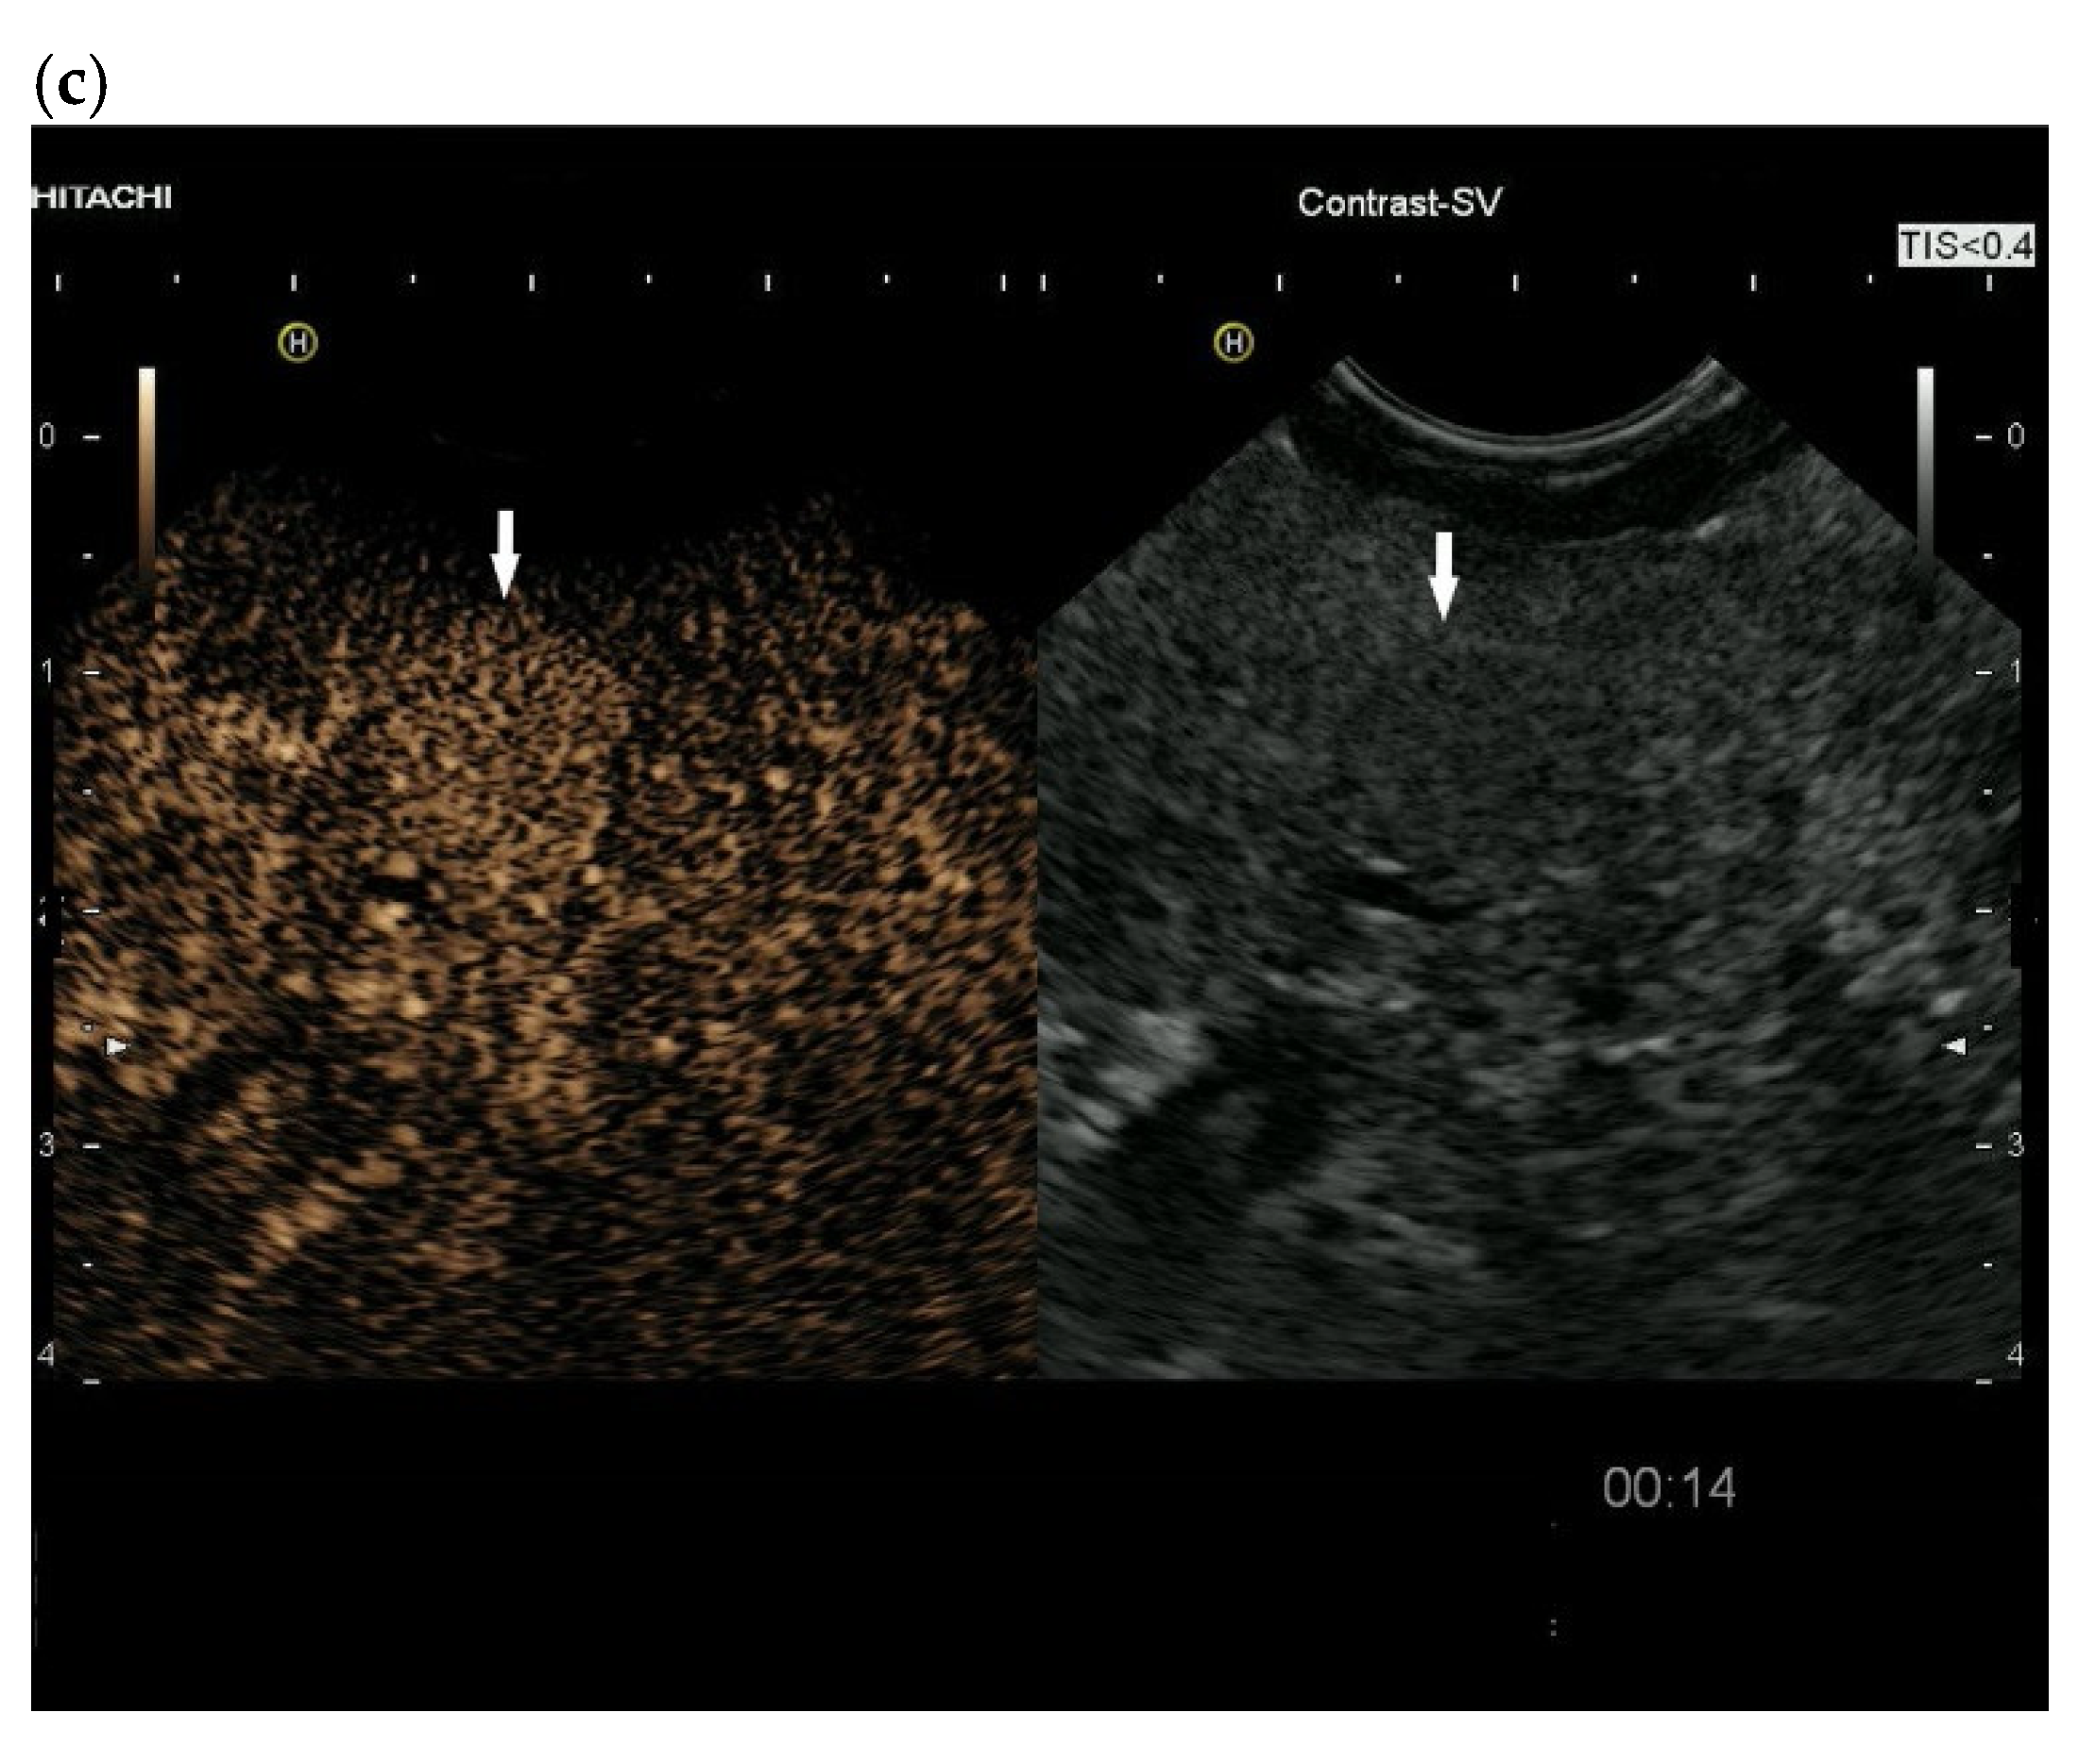

3.4. CEUS and CH-EUS

| RCC metastases [83] (n = 4) | Hyperenhancement, Early | Hyperenhancement | ||

| RCC metastases [61] (n = 3) | Hyperenhancement, homogeneous pattern | Slow washout | ||

| RCC metastasis [86] (n = 1) | Hyperenhancement, Inhomogeneous pattern | No washout | ||